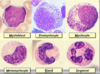

ID cells a, b, e, & f

a. promyelocyte

b. neutrophilic myelocyte

e. neutrophilic band cell

f. segmented neutrophil

I cells b, c, d, e, & g

b. neutrophilic metamyelocyte

c. band neutrophil

d. segmented neutrophil

e. segmented neutrophil

g. neutrophilic metamyelocyte